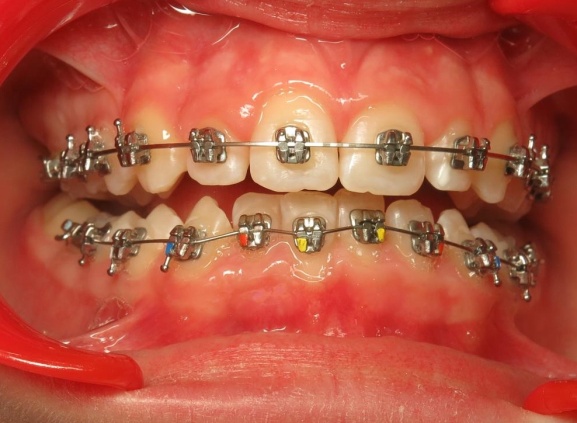

1 - Avant et après traitement

Un traitement orthopédique a permis d’optimiser la croissance des bases osseuses, offrant des conditions favorables à l’évolution de la dentition. Le traitement multiattaches a ensuite aligné les dents sur des structures squelettiques correctement développées.

Le traitement a d’abord consisté à corriger le décalage entre les bases osseuses des mâchoires par une phase orthopédique. Une fois cet équilibre rétabli, un appareil multiattaches a été mis en place pour aligner les dents sur des bases désormais bien positionnées. La dernière étape a permis de peaufiner les contacts entre les dents afin d’obtenir une occlusion fonctionnelle et stable.